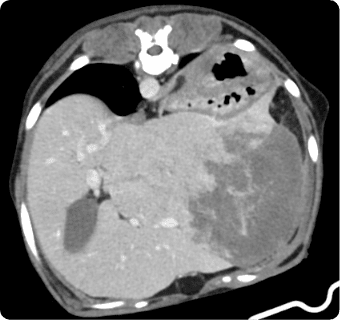

빠른 촬영속도를 통해 마취시간을 최소화 하며, 선명한 3차원 영상을 구현합니다.

종양, 전이평가, 선천적 혈관 기형 등 여러 질환의 조기 발견 및 환자상태를 평가합니다.

간, 비장, 소화기, 콩팥, 방광, 부신의 종양, 간문맥전신단락, 복강 내 실질 장기 평가, 요로결석에 의한 폐색 평가